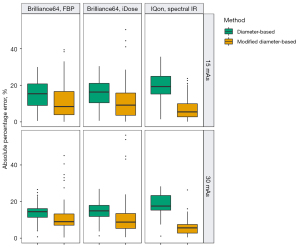

Absolute percentage error reduction by the new method

In the LSCT001 series of scans, in which 10-mm nodules were scanned and measured under six different settings, the APE was significantly less with the modified diameter-based volume calculation than with the diameter-based volume calculation (Wilcoxon signed-rank test, P<0.05) under each scan setting (Figure 4 and Table 1). In the Lungman series of scans, in which 5-, 8-, 10-, and 12-mm nodules were scanned with different reconstruction algorithms, the APE was significantly less with the modified diameter-based calculation than with the diameter-based calculation for all nodule sizes (Wilcoxon signed-rank test, P<0.001) and each reconstruction algorithm (Figure 5 and Table 2). The APE median increased as the size of the nodule decreased. This trend was statistically significant (Jonckheere-Terpstra test, P<0.001), regardless of the reconstruction algorithm (FBP and IMR) and volume measurement method (diameter-based and modified diameter-based volume calculations).

The present study demonstrated a substantial difference between volumes derived from diameter-based and voxel-counting methods in synthetic spherical nodules; however, this difference was significantly reduced when one pixel spacing was added to the diameter in each axis as a modification to the diameter-based volume calculation.

The inter-scan variability for the volume is as much as ±25% (13,14); accordingly, 25% has been used in some screening studies as the minimal percentage volume change signifying true growth (3,4,15). In our study, the APE of the diameter-based volume relative to the voxel-counting volume was substantial, and increased as the nodule size decreased, with medians exceeding 25% for 5- and 8-mm nodules. Our phantom study results may be applied to clinical settings. Unless consistent volume measurement method is used, follow-up images of small nodules can be prone to false interpretation: nodule growth or shrinkage. To minimize those confusing interpretations and avoid inconsistent nodule management, an adequate conversion should be applied when comparing diameter-based and voxel-based volumes of a pulmonary nodule. Among several factors that can cause disparity between two volume assessments, we focused on the loss of at least one pixel spacing when measuring the physical distance between two voxels, and added one extra pixel spacing to the diameter in each axis during the volume calculation. As a result, this simple new method significantly reduced the APE to a median of around 25% for 5- and 8-mm nodules, which would provide more consistent nodule management.